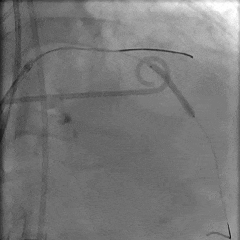

左冠狭窄处行PCI处理